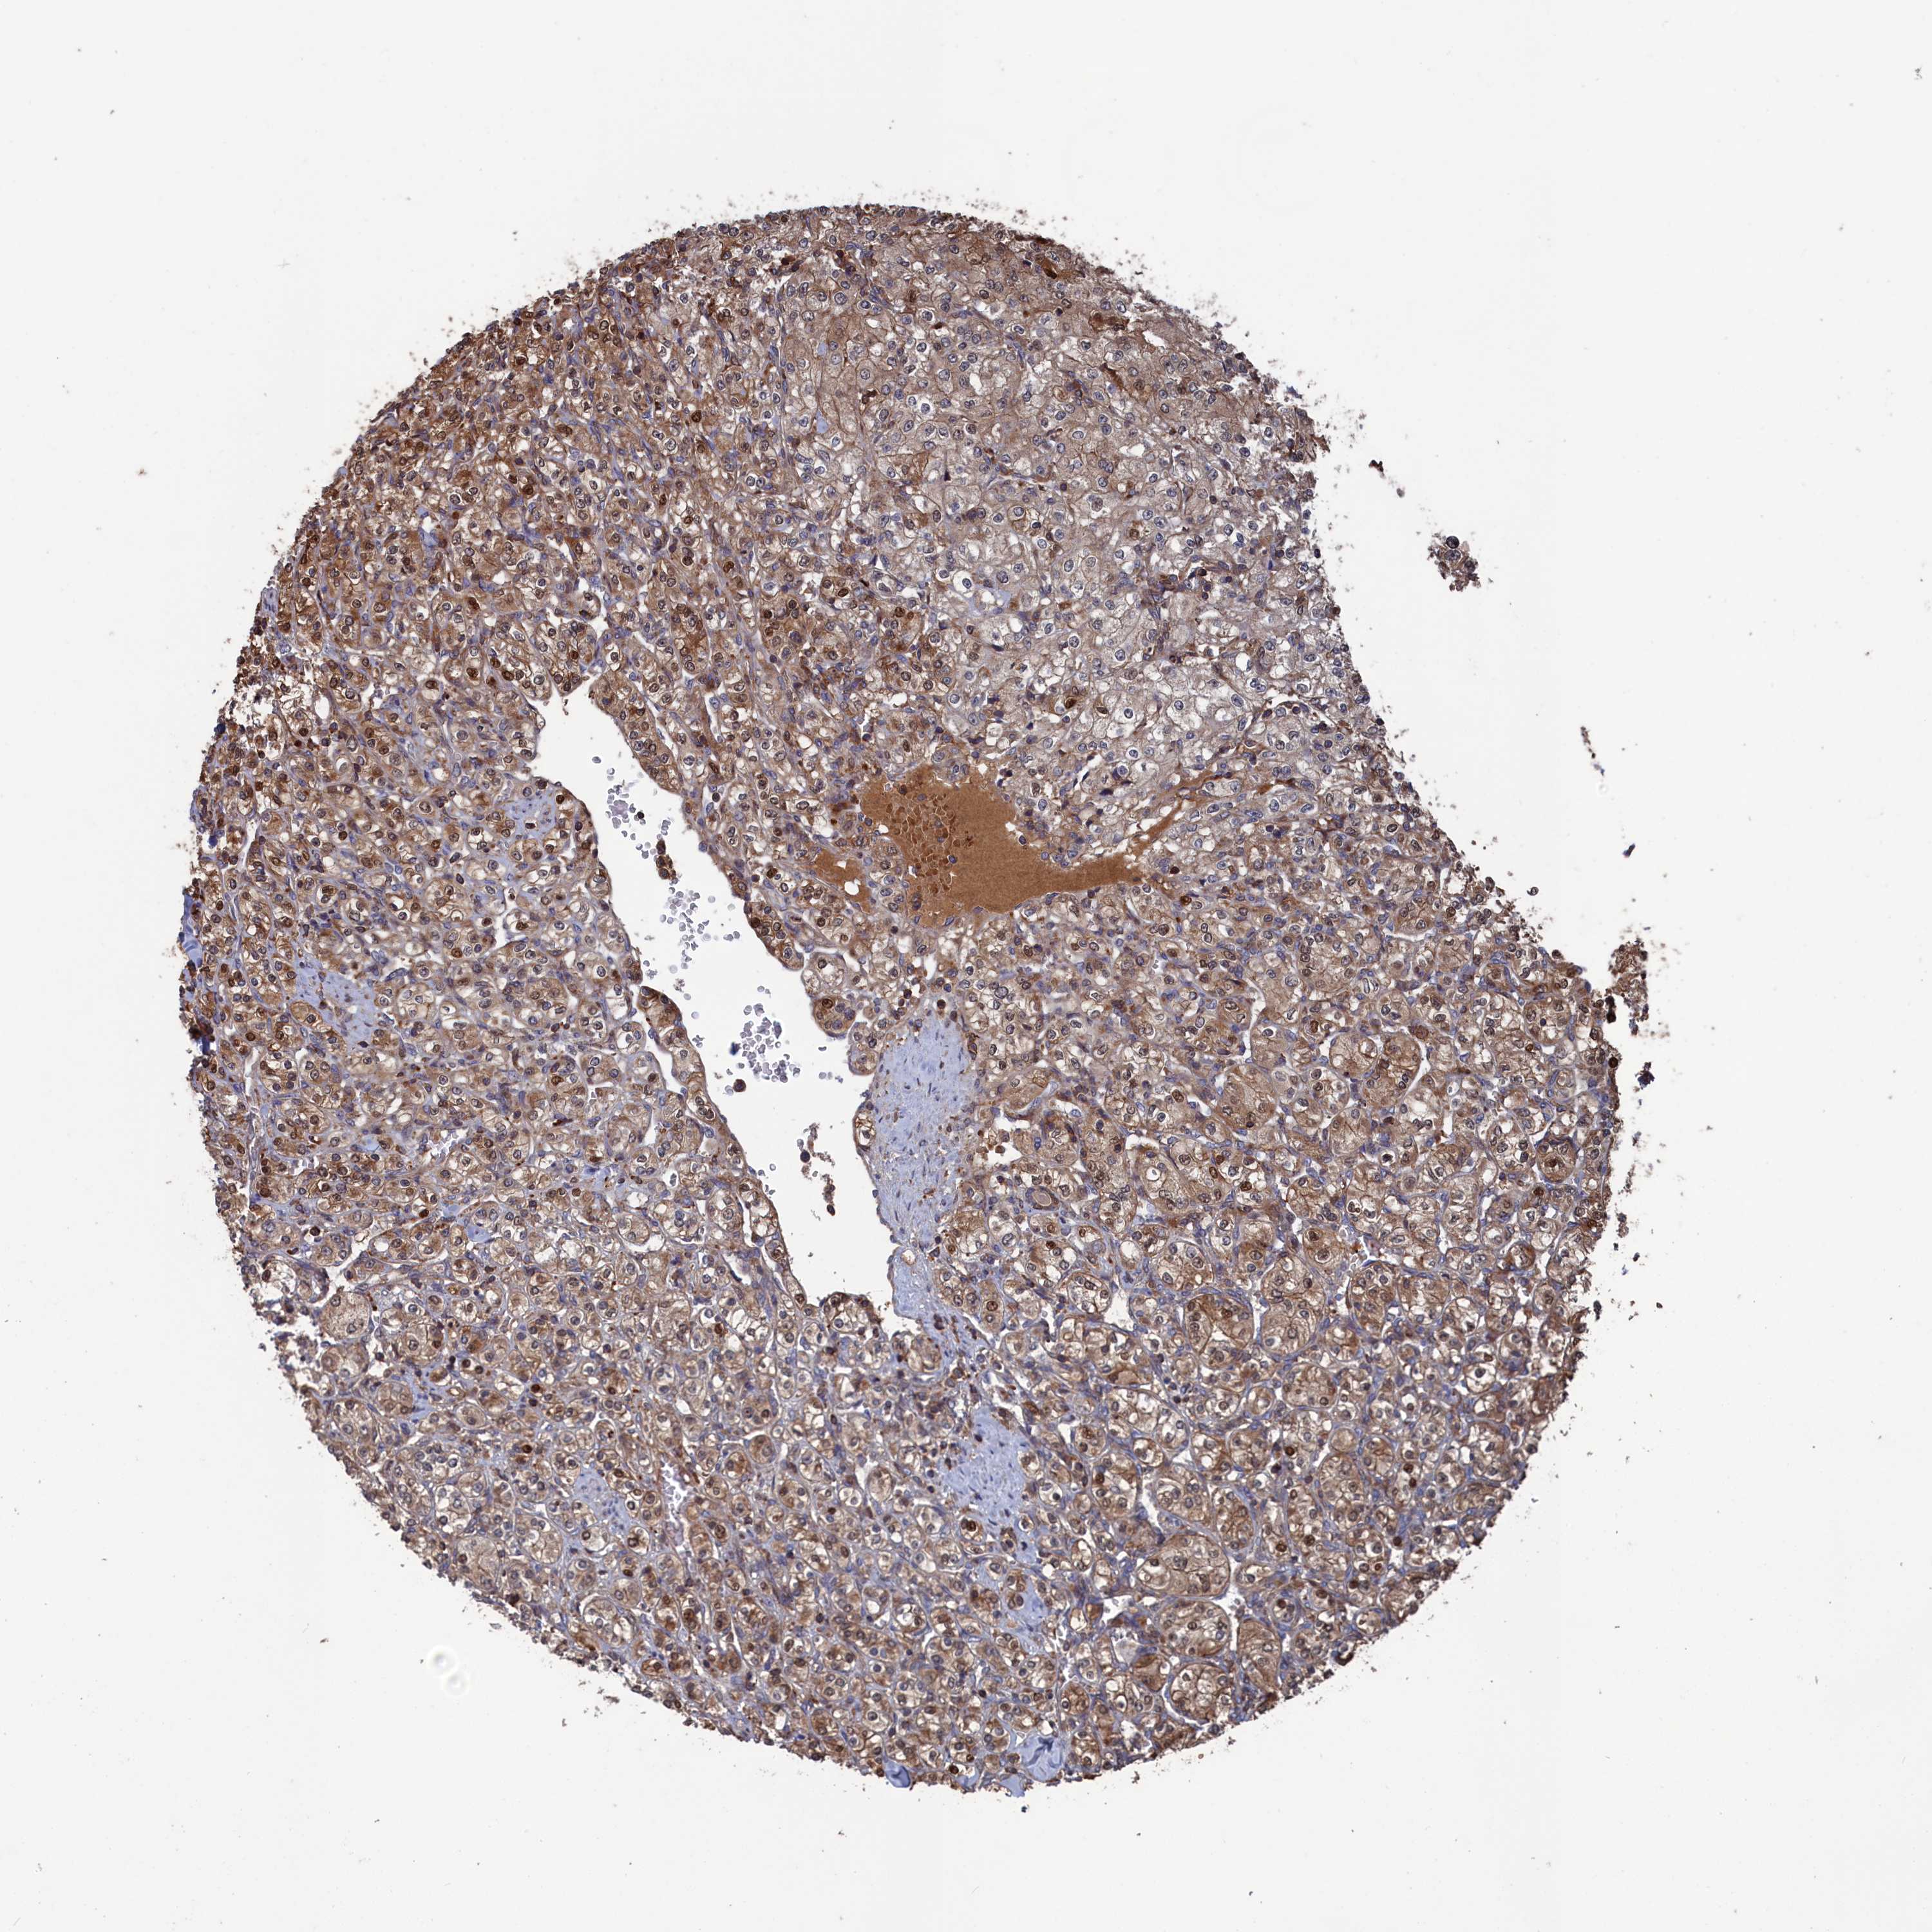

KIDNEY RENAL CLEAR CELL CARCINOMA (VALIDATION) - Interactive survival scatter ploti

The Survival Scatter plot shows the clinical status (i.e. dead or alive) for all individuals in the patient cohort, based on the same data that underlies the corresponding Kaplan-Meier plots. Patients that are alive at last time for follow-up are shown in blue and patients who have died during the study are shown in red.

The x-axis shows the expression levels (FPKM) of the investigated gene in the tumor tissue at the time of diagnosis. The y-axis shows the follow-up time after diagnosis (years). Both axes are complimented with kernel density curves demonstrating the data density over the axes. The top density plot shows the expression levels (FPKM) distribution among dead (red) and alive patients (blue). The right density plot shows the data density of the survived years of dead patients with high and low expression levels respectively, stratified using the cutoff indicated by the vertical dashed line through the Survival Scatter plot. This cutoff is automatically defined based on the FPKM cutoff that minimizes the p-score. The cutoff can be changed by dragging the vertical line or by entering a cutoff value in the square labeled "Current cut-off".

Under the Survival Scatter plot the p-score landscape (black curve; left axis) is shown together with dead median separation (red curve; right axis). Dead median separation is the difference in median mRNA expression between patients who have died with high and low expression, respectively. It is calculated as follows: median FPKM expression of dead patients with high expression - median FPKM expression of dead patients with low expression. This is intended to aid the user in visually exploring custom cutoffs and the associated p-scores and dead median separation.

Individual patient data is displayed and can be filtered by clicking on one or more of the category buttons on the top of the page. Categories describing expression level and patient information include: high, low, alive, dead, female, male and tumor stages. The scale of the x-axis can be toggled between linear and log-scale by clicking on the "x log" button. Mouse-over function shows TCGA ID, patient information and mRNA expression (FPKM) for each patient.

& Survival analysisi

Kaplan-Meier plots summarize results from analysis of correlation between mRNA expression level and patient survival. Patients were divided based on level of expression into one of the two groups "low" (under cut off) or "high" (over cut off). X-axis shows time for survival (years) and y-axis shows the probability of survival, where 1.0 corresponds to 100 percent.

PLA2G15 is potential prognostic, high expression is unfavorable in Kidney Renal Clear Cell Carcinoma (validation)

Best expression cut offi

Based on the FPKM value of each gene, patients were classified into two groups and association between prognosis (survival) and gene expression (FPKM) was examined. The best expression cut-off refers the FPKM value that yields maximal difference with regard to survival between the two groups at the lowest log-rank P-value. Best expression cut-off was selected based on survival analysis .

When clicking on this number, the vertical dashed line indicating cut-off, the interactive survival plot, and the Kaplan-Meier curve will be adjusted to show results based on the best expression cut-off.

: 34.29

P scorei

Log-rank P value for Kaplan-Meier plot showing results from analysis of correlation between mRNA expression level and patient survival.

N/A

5-year survival highi

5-year survival for patients with higher expression than the expression cutoff.

For melanoma and glioma, 3-year survival is shown.

5-year survival lowi

5-year survival for patients with lower expression than the expression cutoff.

TCGA RNA samplesi

RNA-seq data is reported as average FPKM (number Fragments Per Kilobase of exon per Million reads), generated by the The Cancer Genome Atlas (TCGA) .

Normal distribution across the dataset is visualized with box plots, shown as median and 25th and 75th percentiles. Points are displayed as outliers if they are above or below 1.5 times the interquartile range. FPKM values of the individual samples are presented next to the box plot.

Average pTPM 27.0

Number of samples 100